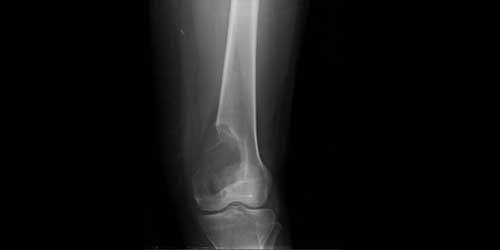

ADAMANTINOMA

It is a rare malignant tumor of bone (less than 1% of malignant tumors of bone origin). It is a low-grade, slow-growing tumor that rarely metastasizes to other organs (especially the lungs).